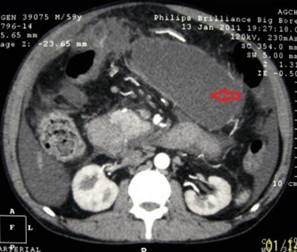

A 59-year-old male presented with painless progressive distension of abdomen of three months duration. He had been consuming 30 g of alcohol daily for the last 20 years. Clinically he was anicteric, afebrile and had tense ascites. The hematological and biochemical investigations revealed hemoglobin of 14.4 g/dL (reference range: 13.0-17.0 g/dL), white blood cell count of 10,500 cells/mm3 (reference range: 4,000-10,000 cells/mm3) (70% polymorphonuclear cells), bilirubin of 0.9 mg/dL (reference range: 0-1 mg/dL), AST of 60 IU/L (reference range: 10-42 IU/L) and ALT of 53 IU/L (reference range: 10-40 IU/L); rest of the blood parameters were normal. Abdominal computed tomography (CT) revealed enlarged caudate and left lobes of liver with relatively smaller right lobe, heterogeneous pancreatic parenchyma, collaterals and marked ascites (Figure 1). Ascites was drained and fluid analysis revealed total leukocyte count of 3,360 cells/mm3 (60% polymorphonuclear cells), protein of 1.0 g/L, albumin of 0.2 g/L, amylase of 116,963 IU/L and adenosine deaminase of 7 U/L. Ascitic fluid cultures were negative. Esophagogastroduodenoscopy showed grade II esophageal varices, small gastric fundal varix and mild portal hypertensive gastropathy. Endoscopic ultrasound (EUS) revealed evidence of chronic pancreatitis and ascites. Diagnosis of internal pancreatic fistula was made and the patient was taken up for endoscopic retrograde cholangiopancreatography (ERCP). Magnetic resonance cholangiopancreatography (MRCP) could have delineated the pancreatic ductal anatomy but not done because of a definite diagnosis of pancreatic ascites due to high fluid amylase in presence of CT scan and EUS evidence of chronic pancreatitis. Pancreatogram revealed a leak from distal part of pancreatic duct (Figure 2). Pancreatic sphincterotomy was done. A cannula was placed next to the fistula, flushed with normal saline and one mL of N-butyl-2-cyanoacrylate glue (Histoacryl®, B. Braun, Tuttlingen, Germany) was injected at the fistula site. Immediately after injection of glue, there was a bit of resistance noted on attempt to withdraw the cannula which was removed with a sharp tug. The check pancreatogram revealed sealed leak (Figure 3). A 7 Fr x 9 cm plastic pancreatic stent was placed in the pancreatic duct. The repeat ascitic fluid amylase was found to be 229 IU/L. He subsequently received low dose of diuretics as well and over the next one week ascites has resolved. His pancreatic stent was removed after 3 weeks and check pancreatogram was normal.

Figure 1. CT scan at the level of uncinate process of pancreas showing free fluid, localized fluid collection on left side (arrow) and collaterals around the collection. |